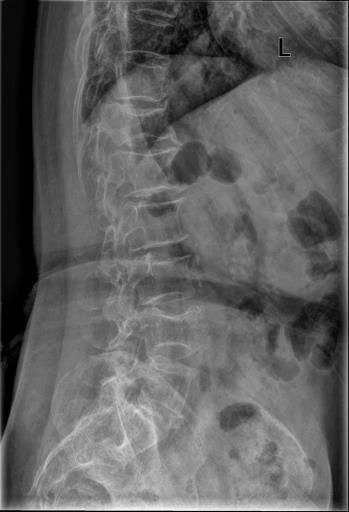

Case13:F,4y;腰痛1月余,加重半月。